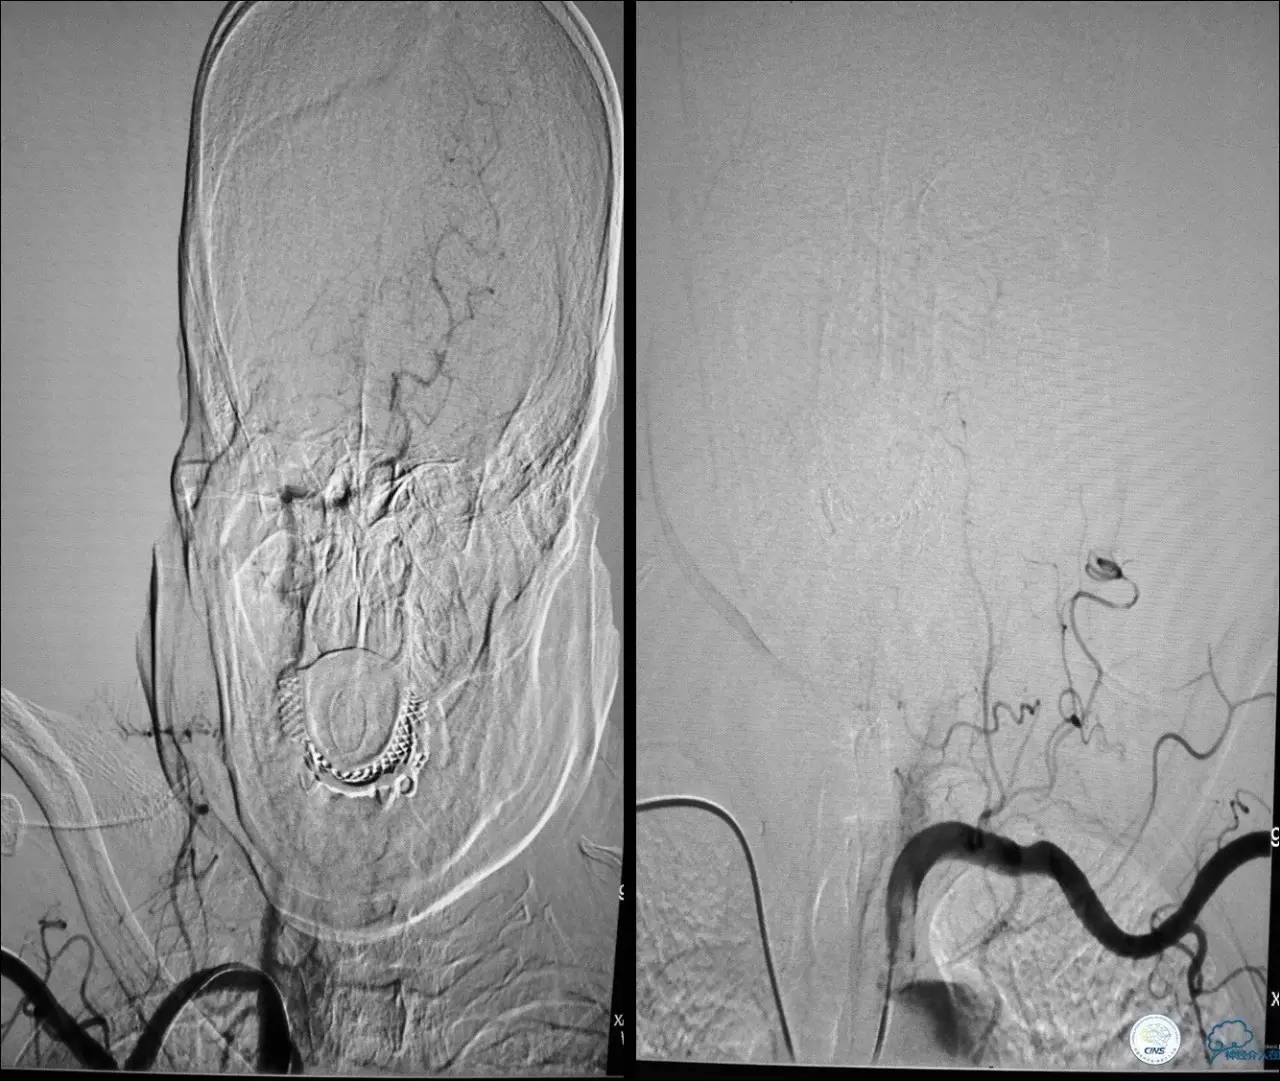

Case 2

》男,74岁。

》主诉:突发左侧肢体抽搐伴口角歪斜两月余,右侧肢体抽搐三天余。

》查体:左上肢肌力Ⅲ级,左下肢肌力Ⅳ级,右侧肢体肌力Ⅴ级。

》既往史:高血压病史。

》患者术后4小时出现右侧肢体无力,伴有癫痫样症状。

》考虑小栓子脱落,术中曾有后扩。